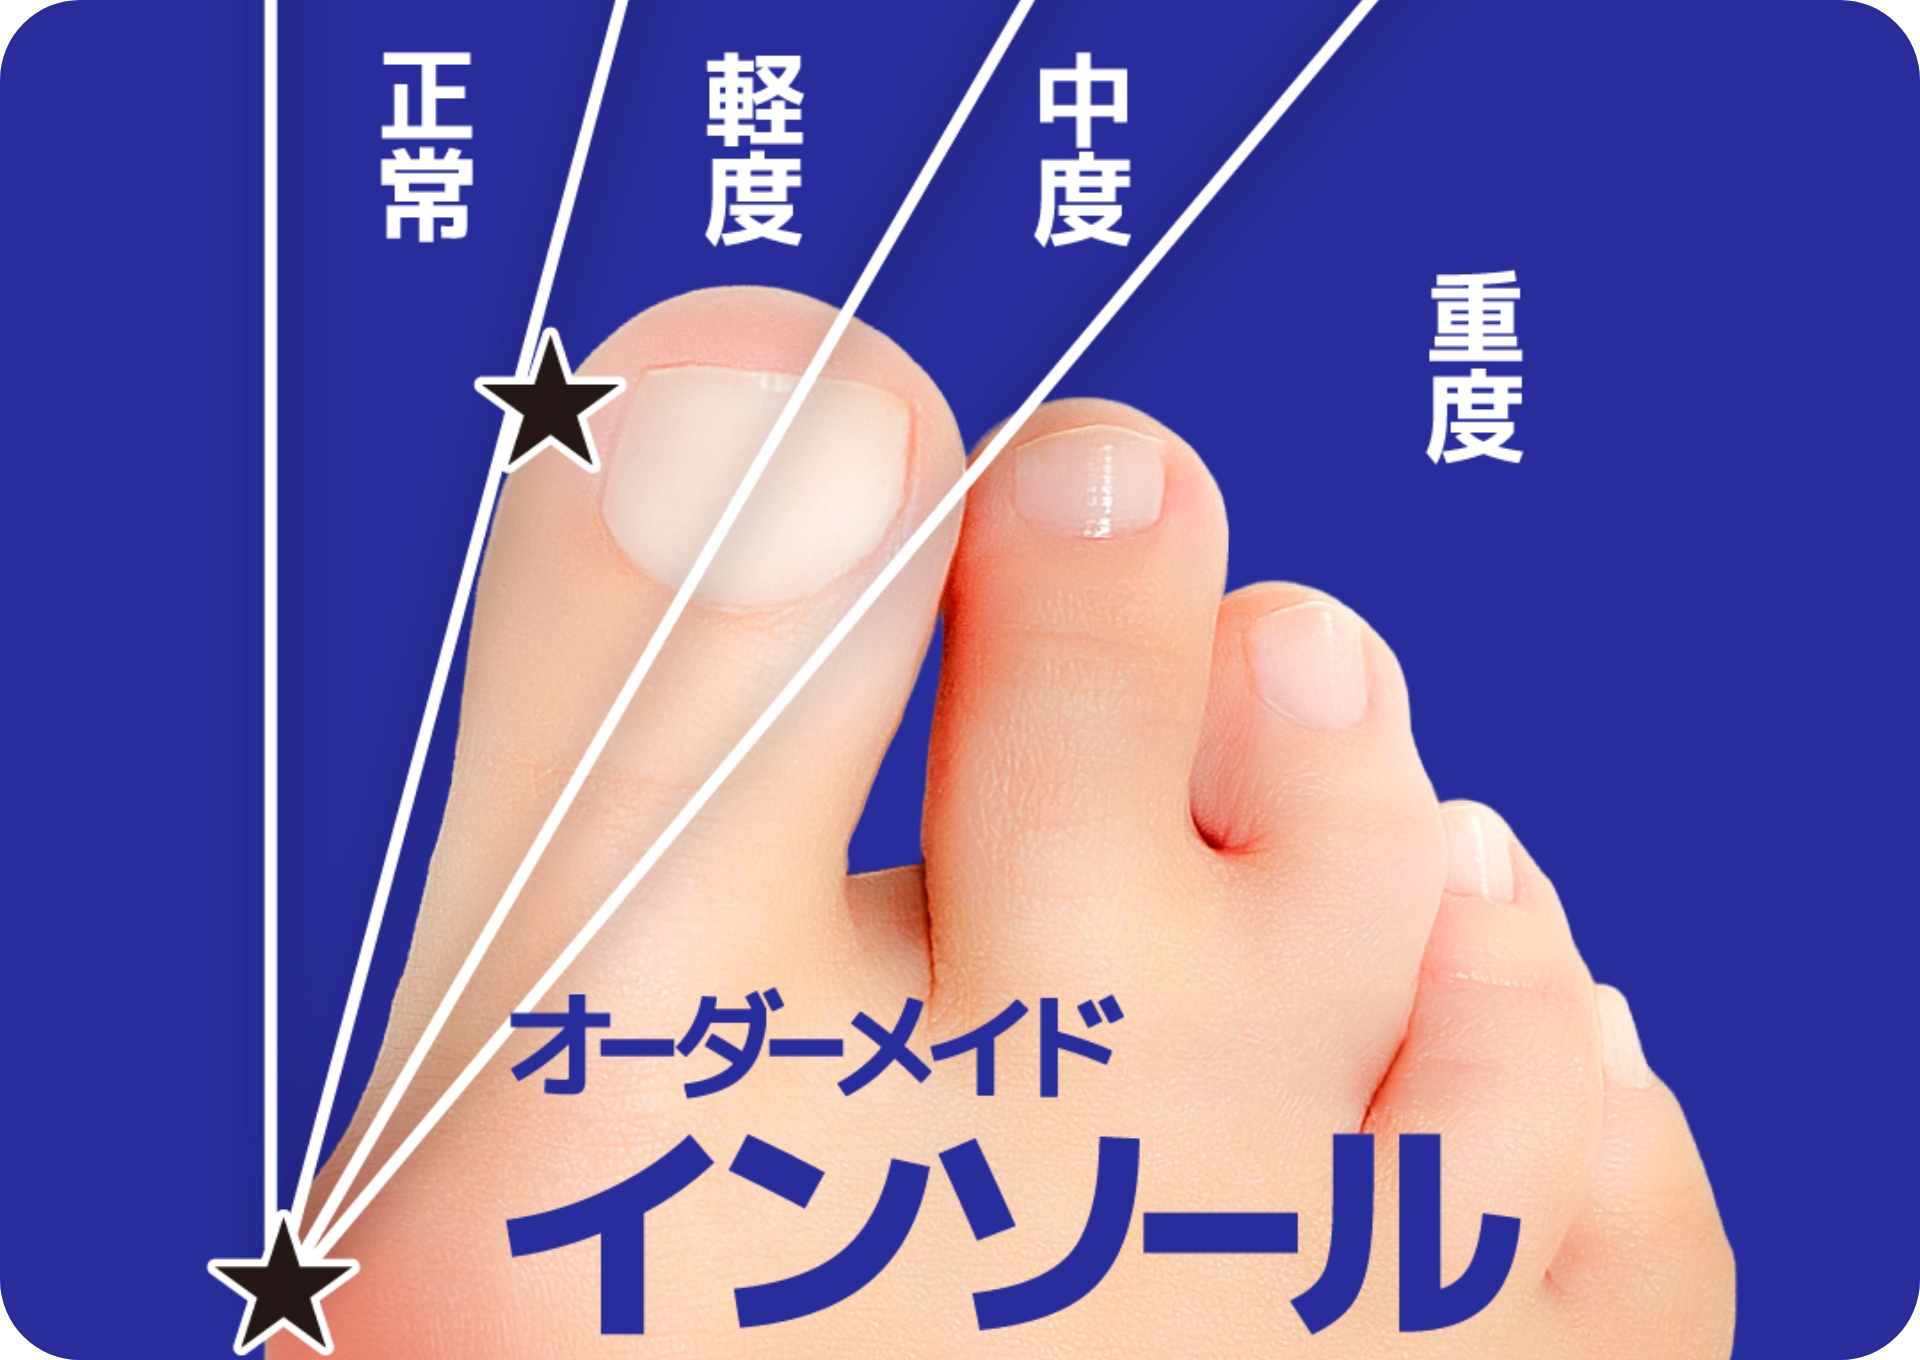

また、股関節の変形によって歩き方が変わり、足に異常がある場合は、海外では主流となっている足病学に基づく「インソール」で、日常生活での歩行を足元から矯正していきます。